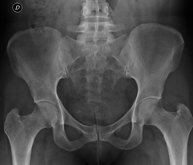

- Pelvis X-ray

This procedure uses X-ray imaging to examine the pelvis, especially the pelvic bones.